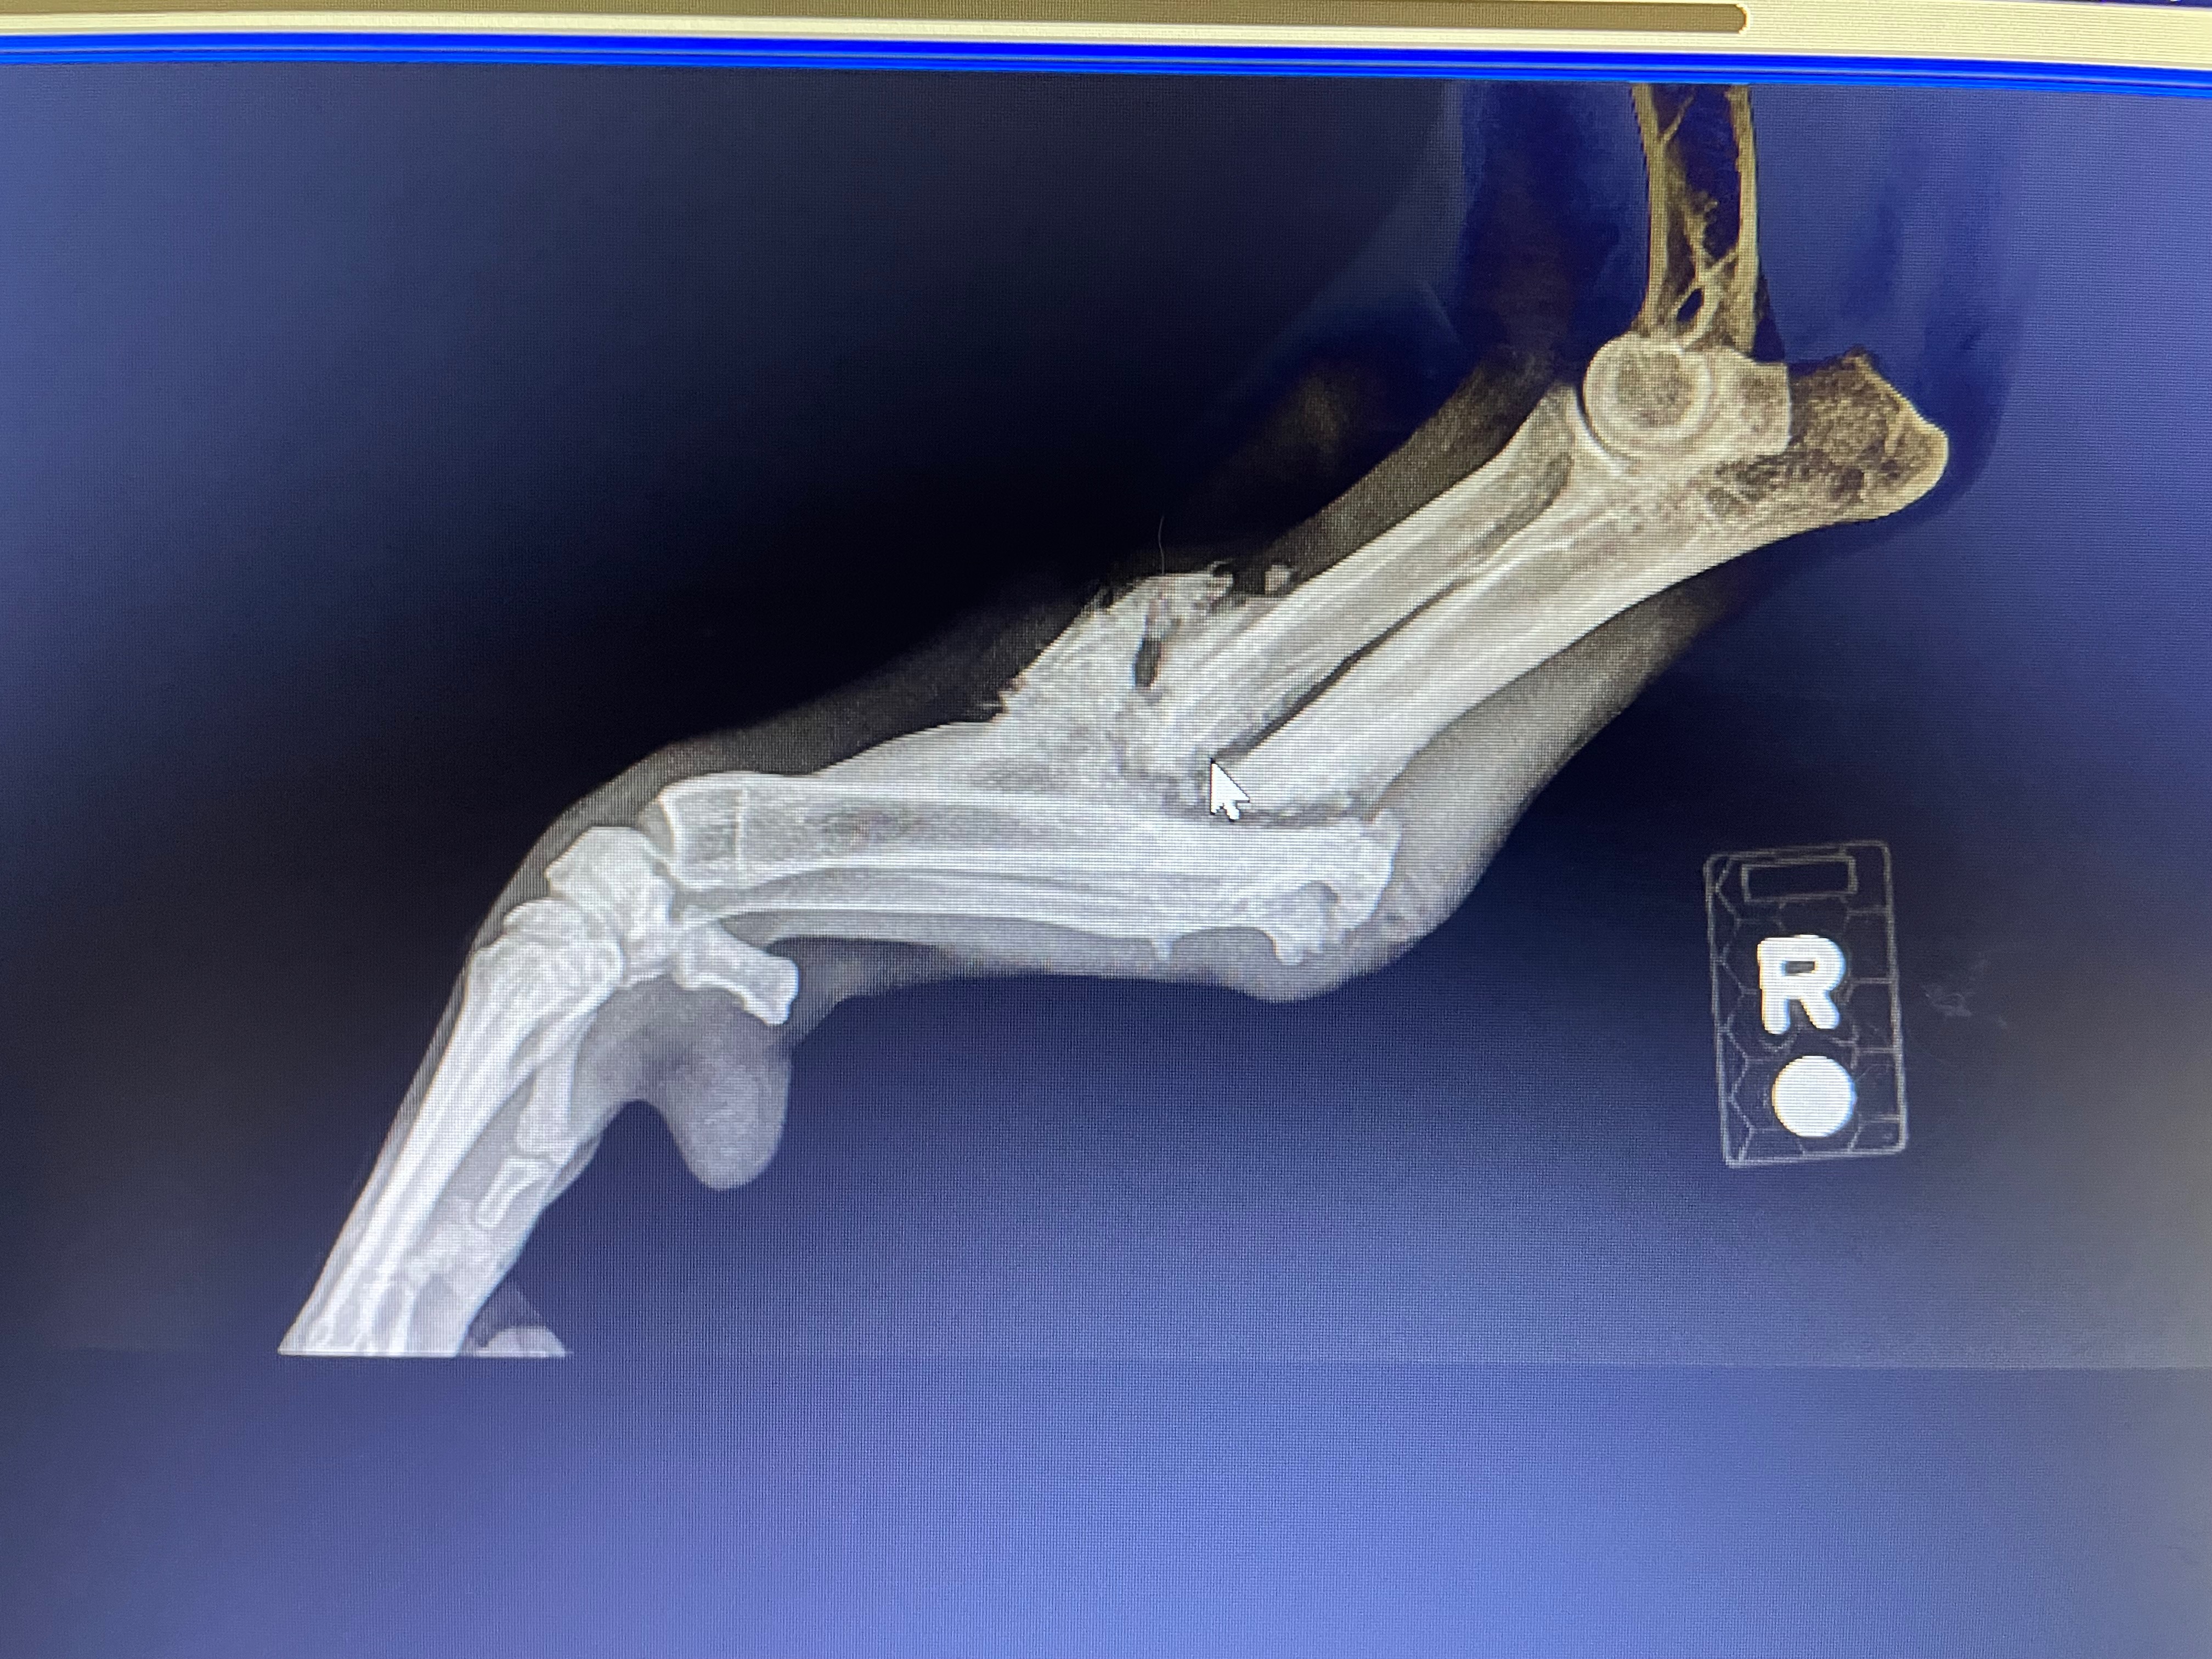

She has a very poorly healed right foreleg fracture that will require repair or amputation.